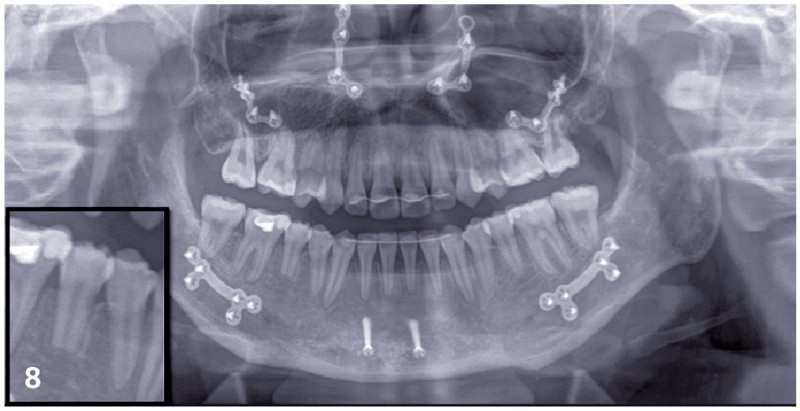

Le choix du plan de traitement s’est porté sur un traitement chirurgico-orthodontique avec réalisation d’une classe II thérapeutique afin de limiter les déplacements dentaires à l’arcade mandibulaire suite au dépistage de rhizalyses idiopathiques sur les prémolaires inférieures (fig. 3) et de l’absence d’encombrement.

Traitement multi-attaches (fig. 4, 5, 6 et 7)

Les extractions orthodontiques ont été réalisées avant le collage de l’appareillage multi-attache Roth 022x.028.

Une séquence d’arcs Niti (.014, .018, .018x.025) a permis de réaliser l’alignement et le nivellement de l’arcade mandibulaire, avant de passer en acier (.019x.025).

La séquence d’arcs a été différente au maxillaire : un acier .014 en by-pass sur les incisives latérales a dans un premier temps été mis en place afin d’éviter tout effet néfaste de vestibuloversion.

Ensuite un arc avec des boucles de fermeture acier .018 a été utilisé afin de permettre le rabitting compte tenu de l’encombrement majeur.

Une fois les espaces d’extractions fermés, nous avons poursuivi le nivellement avec des arcs aciers .016x.022 puis .018x.025 afin de programmer la chirurgie orthognathique.